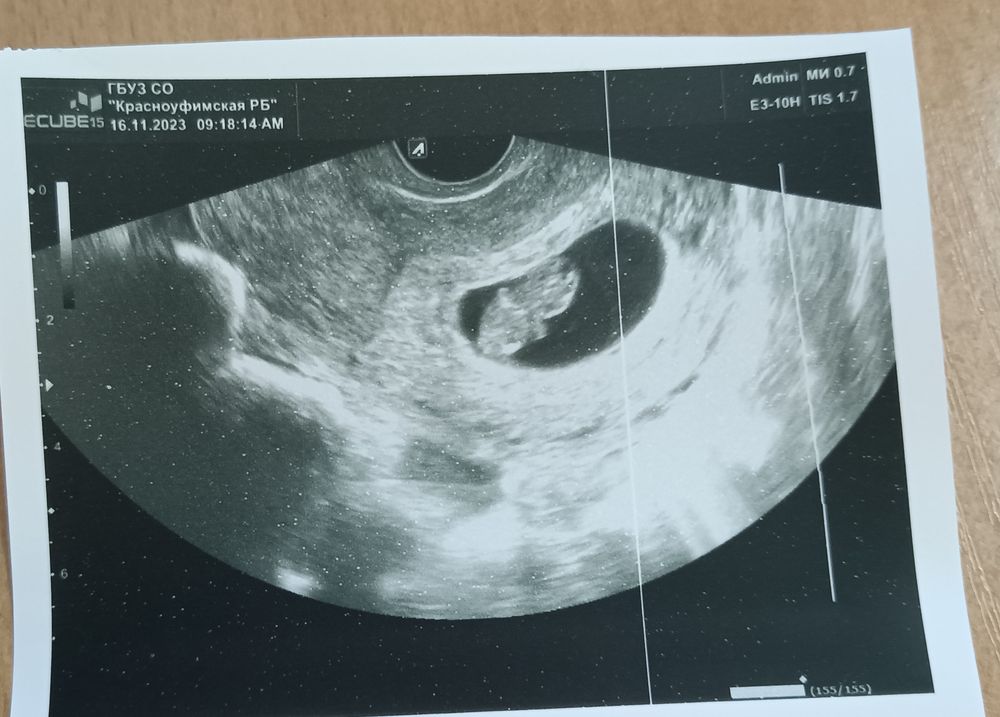

9 недель и 3 дня🤰

Сходила на прием, сделали УЗИ, в итоге, 9 недель и 3 дня. Послушала сердечко, сразу столько воспоминаний о первой беременности. В четверг надо сдать кучу анализов. Скоро на учёт.